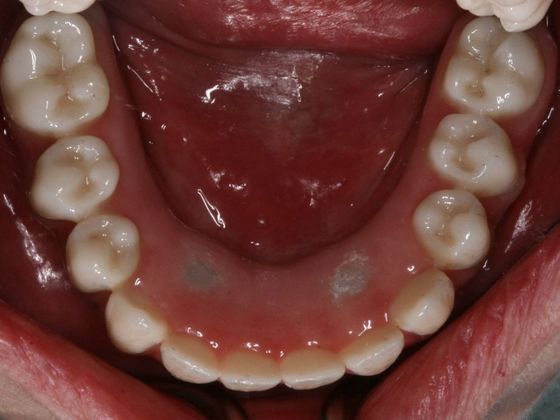

Procedures : extractions, implants, All on 4 , Teeth in a day, no bone grafting and full mouth reconstruction with monolithic zirconia bridges.